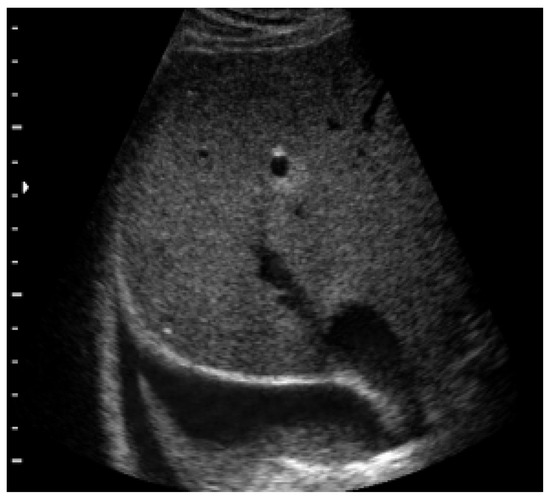

4.6. Pleural Pathologies and Complications of Pneumonia